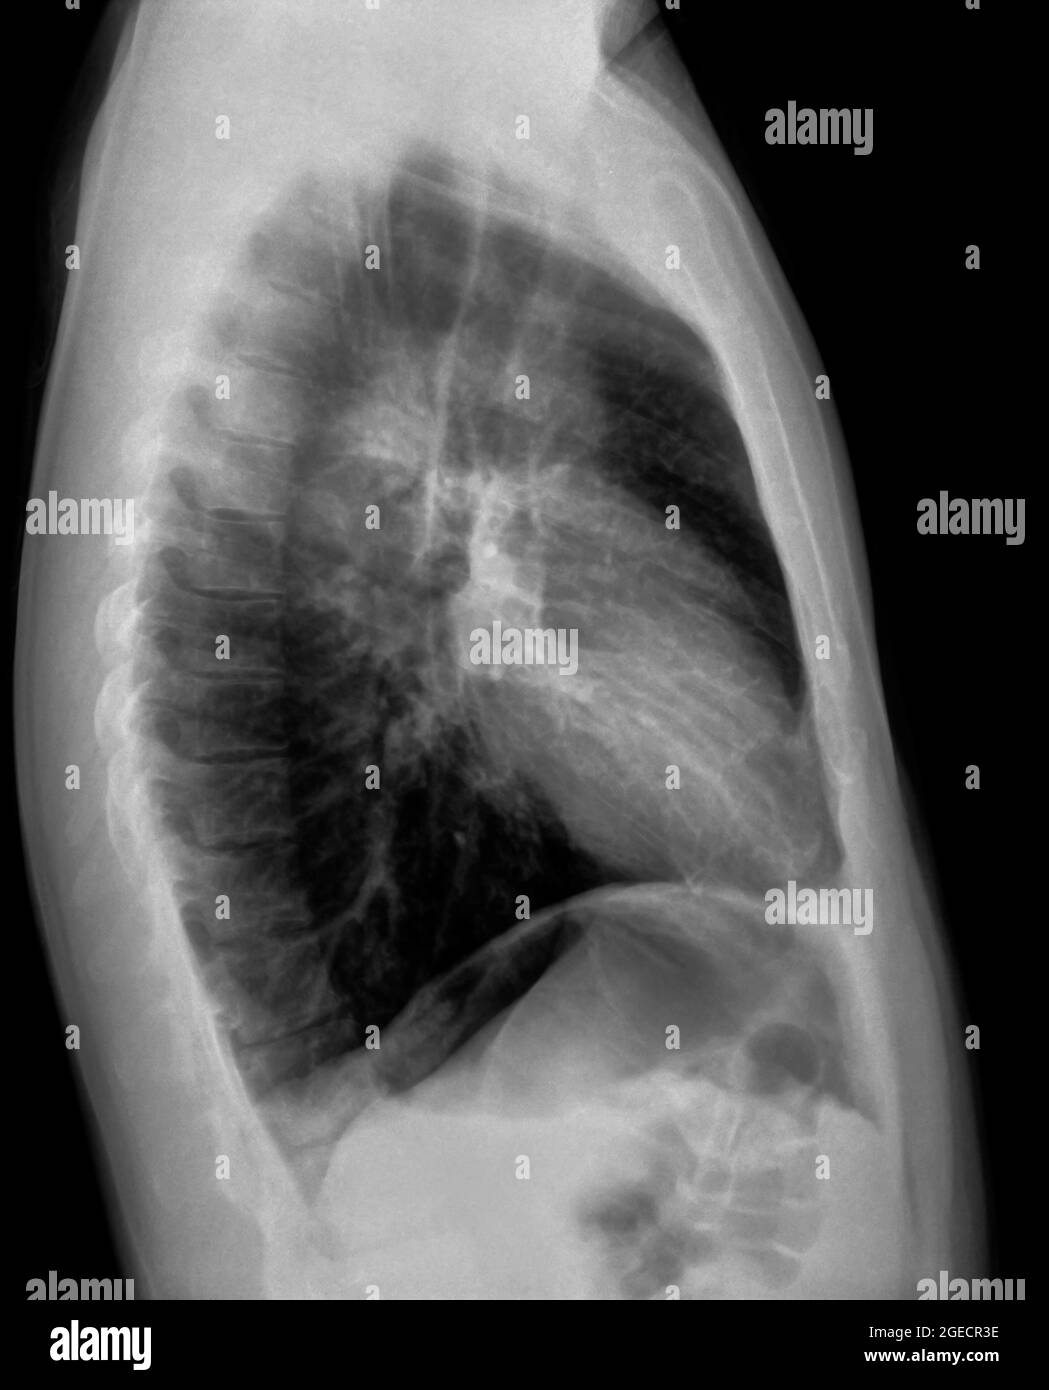

Lateral Chest Xray Normal Chest X Ray 3 Year Old this article lists examples of normal imaging of the pediatric patients divided by region, modality, and age. This can occur with congenital heart disease or congestive heart failure. ( 1) the relative size of a lung or hemithorax, ( 2) the degree of. pulmonary aeration abnormalities are best evaluated on the chest radiograph by observing the following criteria:. Normal Chest X Ray 3 Year Old.